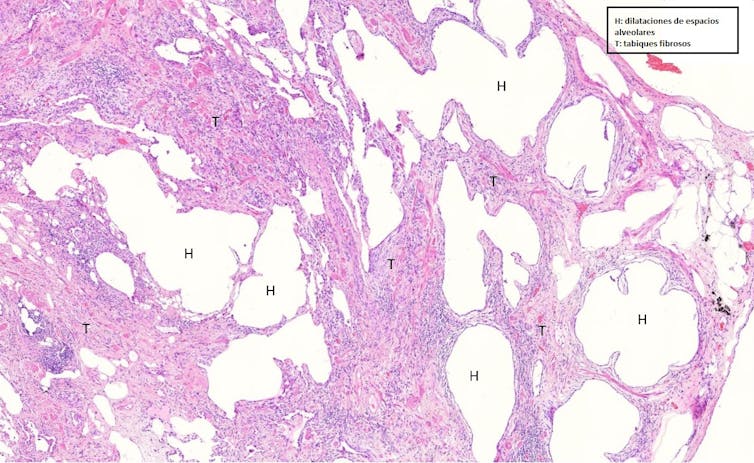

En forma de panal de abeja

La asbestosis se inicia con una fibrosis en torno a los bronquiolos respiratorios y los conductos alveolares, desde donde se extiende hasta afectar el resto del tejido adyacente. El tejido fibroso deforma la arquitectura del órgano y crea lo que se conoce como un patrón morfológico en “panal de abeja”, también denominado panalización. Este patrón es inespecífico, por lo que la historia de exposición al amianto es la clave para el diagnóstico certero de la asbestosis.